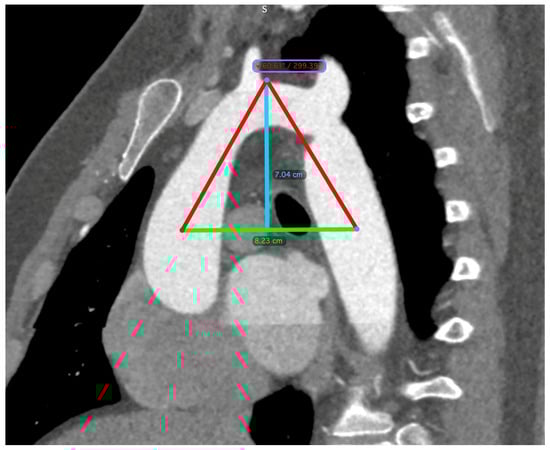

The diagnosis of CoA was established via computed tomography (CT) imaging. Aortic dimensions were meticulously determined through three-dimensional reconstructions, employing oblique angles orthogonal to the vessel’s longitudinal axis. The aortic perimeter was calculated using the formula: perimeter divided by π (where π is approximately 3.14). Measurements were taken at critical anatomical points, including the midpoints of the ascending aorta and descending aorta, both aligned with the right pulmonary artery, the midpoint of the aortic arch (either situated between the common carotid artery and the left subclavian artery or located at the apex of the aortic arch), the isthmus, and the aorta at the diaphragmatic level. A triangle was constructed, linking the arch apex with the midpoints of the ascending and descending aorta, from which the arch angle (vertex angle of the triangle) and arch height and width (base of the triangle) were derived. The arch height was ascertained by the perpendicular distance from the base to the highest midpoint of the arch (Figure 2).

Figure 2. CT scan measurements. A triangle is formed between the apex of the arch (indicated by the blue line) and the midpoints of the ascending and descending aorta (indicated by the green line), which are aligned with the right pulmonary artery. The arch angle was defined as the vertex angle of the resultant triangle, and the arch width was the basal length of this triangle. The perpendicular distance from the basal length to the arch’s apex determined the arch height.